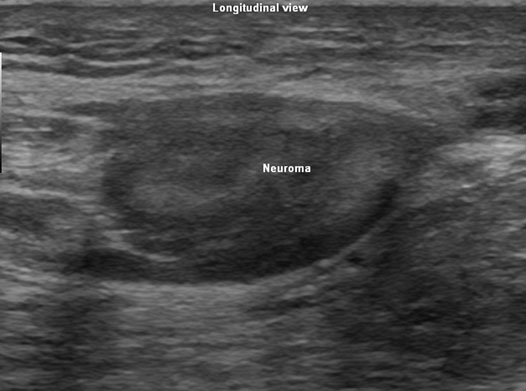

Neuroma appears as an incompressible, oval, bulbous, hypo-echoic structure in continuity with the nerve. Sometimes hyperechoic bands representing intraneural connective tissue are also seen. The margins may be well defined or irregular. Anecdotal report of vascularity changes in tissues surrounding a neuroma has been described.2

Figure 1. Transverse sonographic view of a sciatic stump terminal neuroma appearing as a bulbous hypoechoic structure in continuity with the sciatic nerve.

Depending on the location of the pain and neuroma, a scout scan is performed using a linear array transducer with appropriate frequency, usually in the range of 7–15 MHz depending on the depth of the target. The scan is performed both in the transverse and longitudinal views in the possible direction of the neuroma (Figures 1 & 2). Once the neuroma is identified the nerve is followed proximally and distally to measure the length and width of the neuroma. No scan is complete without a color flow Doppler study to identify the vessels in the neighborhood. This also facilitates in planning a needle trajectory.